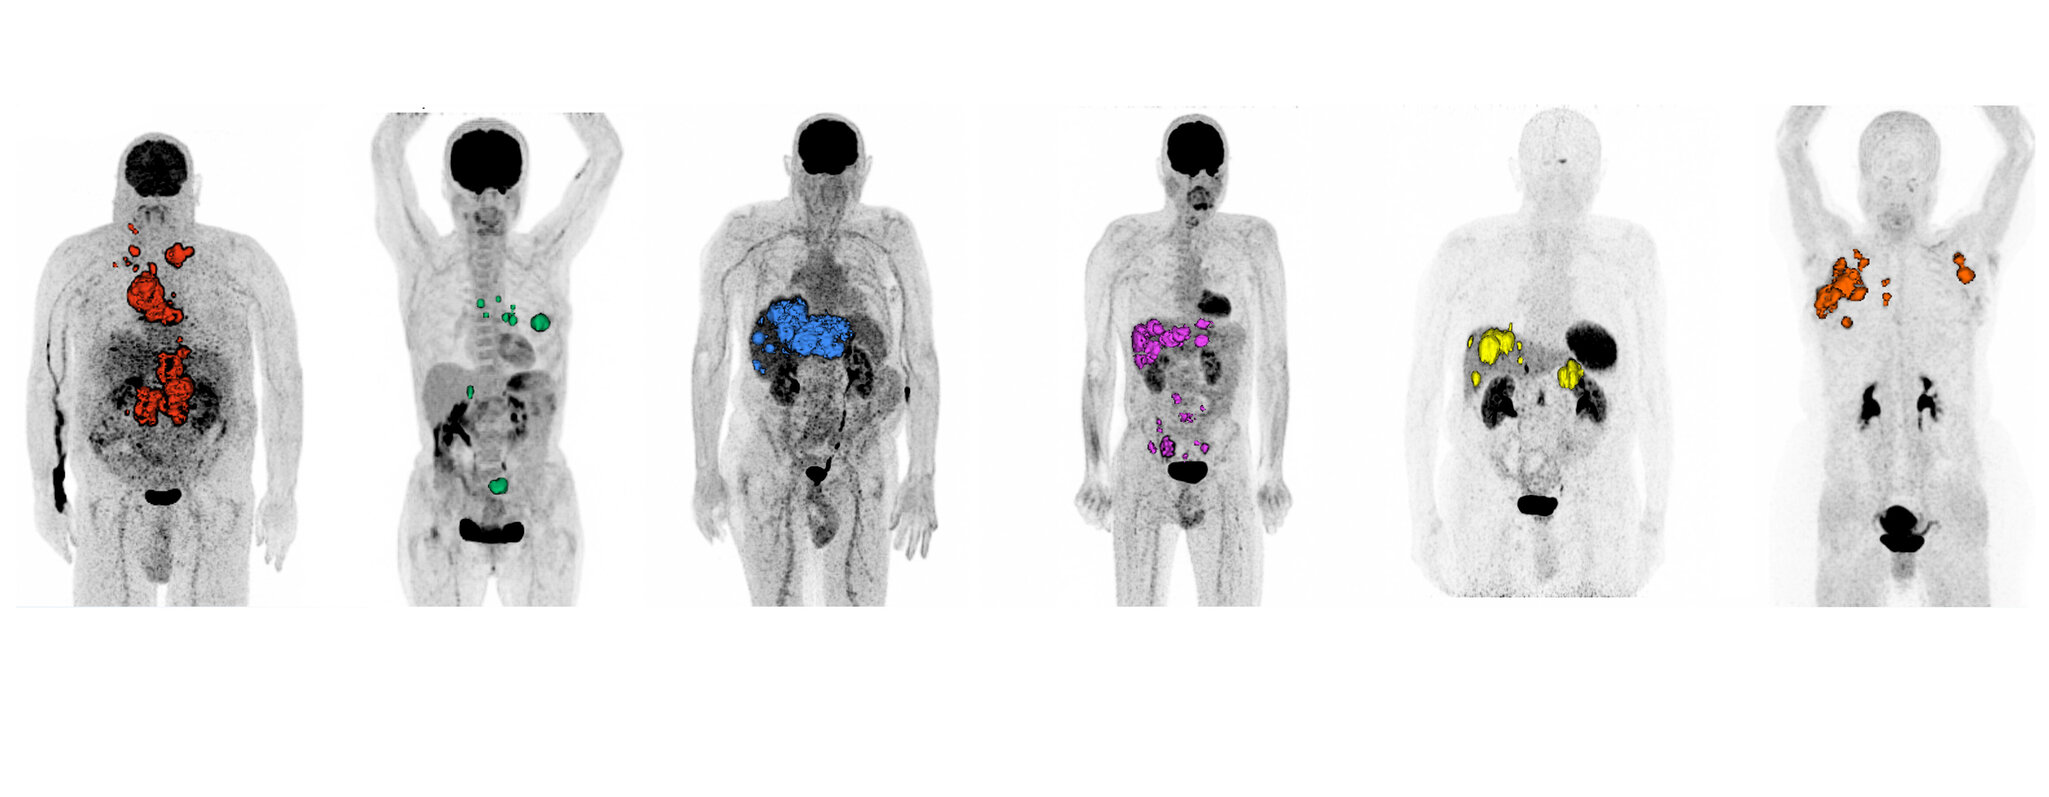

In der Klinik für Nuklearmedizin am UKS beschäftigen wir uns mit den Funktionen von verschiedenen Organen und untersuchen diese fundiert auf Erkrankungen und Störungen. Dabei setzen wir sogenannte Radiopharmaka ein, also Medikamente mit einer sehr geringen Radioaktivität. Meist intravenös verabreicht, werden diese vom Körper in die Stoffwechselvorgänge integriert und sammeln sich in bestimmten Körperorganen oder Körpergeweben an. Hier zerfallen sie und senden je nach bei der Untersuchung verwendetem Radionuklid Strahlung aus, die es uns erlauben, mittels spezieller Geräte, sogenannter Gammakameras Bilder aus dem jeweiligen Bereich zu gewinnen.

So erhalten wir einzigartige Einblicke in den Stoffwechsel und die Funktion verschiedener Gewebe und Organe, die mit keinem anderen Verfahren möglich sind. Ob Krebserkrankungen, Herzerkrankungen, Entzündungen oder neurologische Störungen, sie alle lassen sich unter Umständen mittels der Nuklearmedizin frühzeitig erkennen.